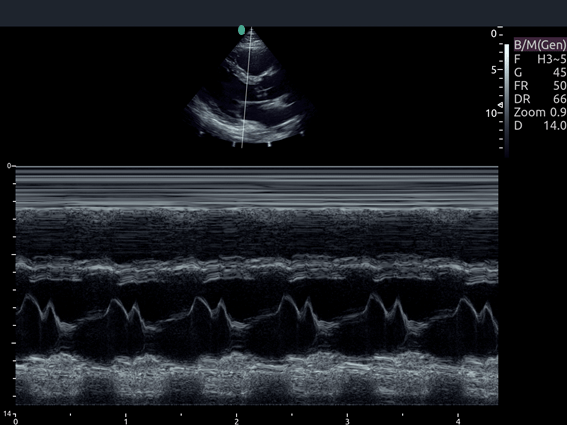

Invictus E5

O ultrassom Invictus E5 apresenta um design moderno e exclusivo, com perfeito fluxo de trabalho e interface intuitiva.

Dentre suas características inovadoras, podemos destacar a tela em LCD com rotação de 60° para ambos os lados, para otimização da visualização durante os exames; tela touch screen com menu totalmente customizável; painel de controle totalmente selado para facilitar limpeza e desinfecção da superfície, o que o torna referência para ser utilizado principalmente em Centro Cirúrgico.

Apresenta excelente qualidade de imagem, trabalho otimizado através de presets pré-determinados, sensibilidade e eficiência em aplicações de Point of Care e portanto, uma perfeita relação custo benefício.